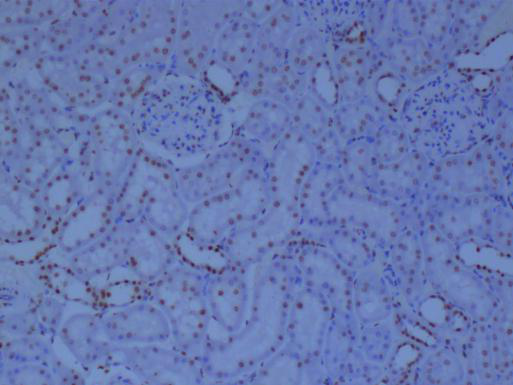

冰凍切片還可以用于免疫組化研究。通過冰凍切片技術(shù),研究人員可以制備含有特定抗原的組織切片,進(jìn)而利用免疫組化方法檢測和分析抗原的表達(dá)情況。這對(duì)于研究細(xì)胞的生物學(xué)功能、疾病的發(fā)生機(jī)制以及藥物的療效評(píng)價(jià)具有重要意義。